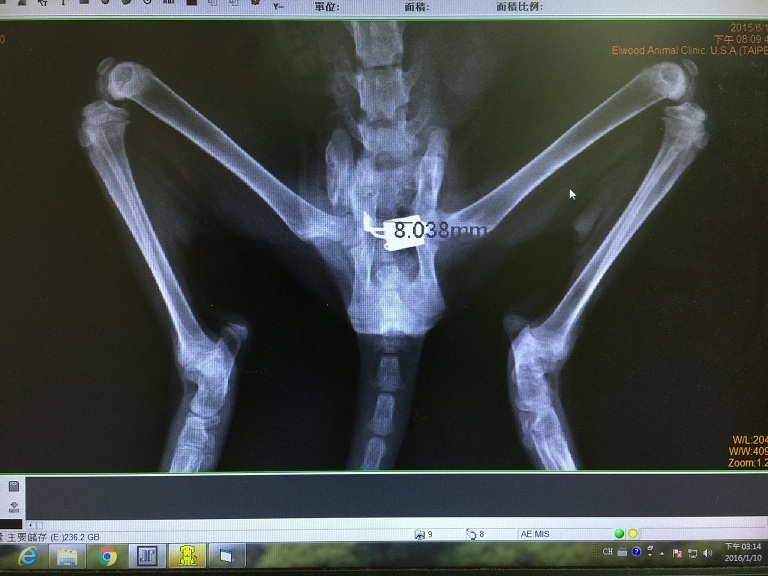

主題: 氣體麻醉結紮的艾咪 申請者姓名: 臺北市支持流浪貓絕育計劃協會 花色: 申請日期: 2016-01-14 12:44:27 申請者部落格: 申請者臉書網址: 所在縣市/合作醫院: 台北市/其他院所醫助專案(醫院請先MAIL溝通) 治療費用: 6100元 需求人數: 15人 已結案 (2024-06-01 13:42:34) 報名人員: Yuu Ki(已付款)、林琦 x6(已付款)、茶課啊(已付款)、lazymimicat(已付款)、Eric Chien(已付款)、Ray0322(已付款)、Mia(已付款)、Pororo Mei(已付款)、lottieshow(已付款)、Will Lin、Gabriella Liu(已付款)、 候補人員: 動物病情說明: 艾咪在還很小的時候發生了車禍,

因此造成骨盆左右腸骨骨折,

且脊椎也有受到傷害。

當時艾咪因為骨盆左右腸骨骨折,

導致骨盆最狹窄處為4mm,

在經過醫生手術之後,

才使得最狹窄處變寬為8mm。

但即使如此,

排便不順暢的問題還是一直困擾著艾咪...

因為正常的貓咪需要10mm以上的骨盆寬度,

才能夠正常順利的排便,

所以目前骨盆只有8mm的艾咪,